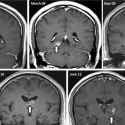

Picrel: gay brain worms